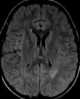

Subacute white matter encephalitis

Subacute sclerosing panencephalitis (SSPE)—also known as Dawson disease—is a rare form of chronic progressive brain inflammation caused by slow infection with certain defective strains of hypermutated measles virus. The condition primarily affects children, teens, and young adults. [Source: Wikipedia ]